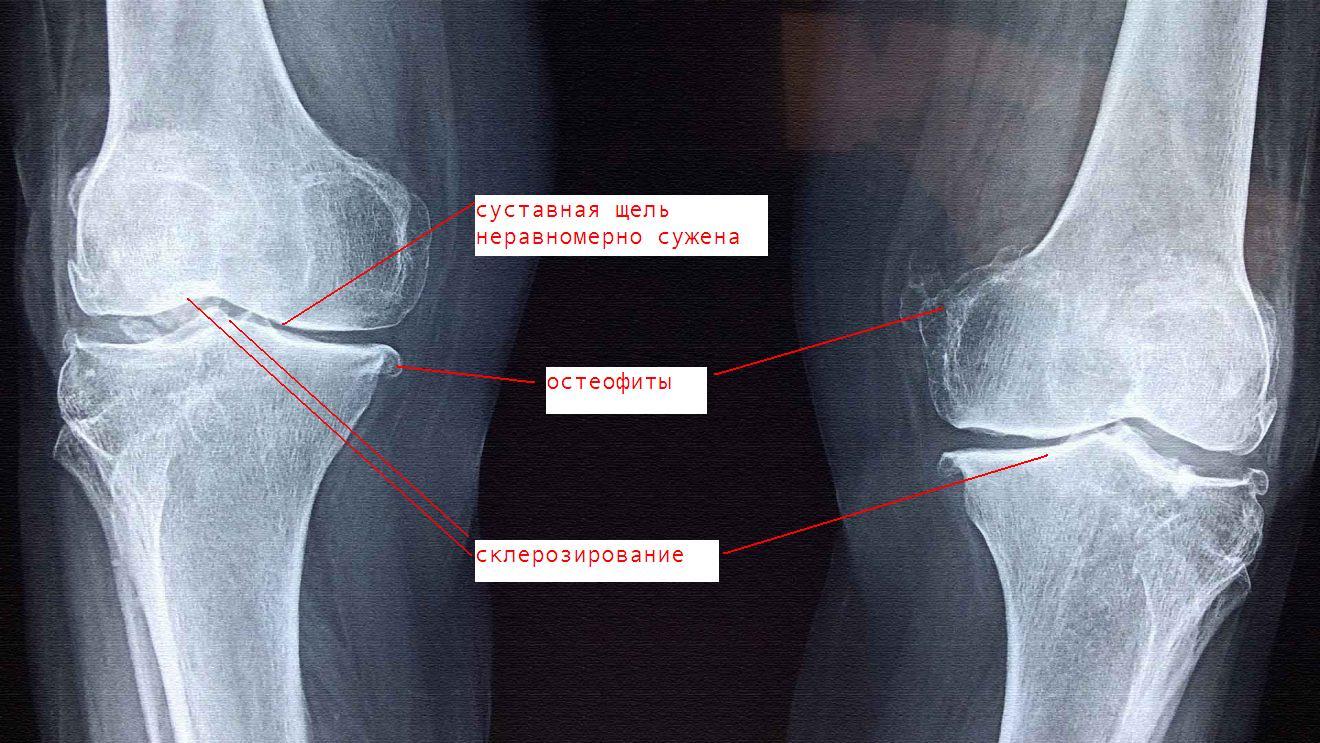

Медицинские снимки: рентген коленного сустава при остеопорозе